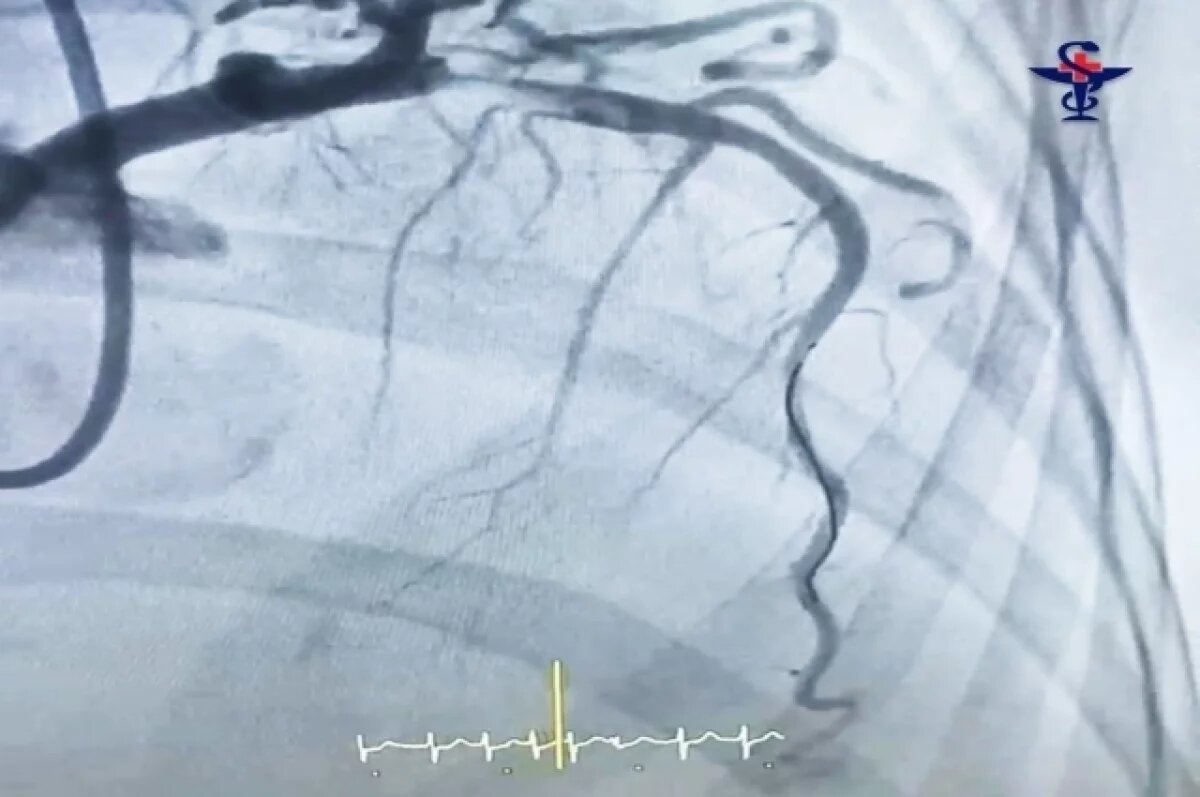

В Александро-Мариинской клинической больнице врачи успешно провели сложнейшую операцию по спасению жизни женщины с обширным инфарктом миокарда в острой форме. Пациентка поступила в экстренном порядке и была незамедлительно направлена в рентгеноперационную.В ходе коронарографии – контрастного исследования сосудов сердца был обнаружен крупный тромб, практически полностью блокировавший кровоток в коронарной артерии. Это критическое состояние угрожало жизни пациентки.Тромб был необычайно большим и протяженным. Однако, благодаря профессионализму медицинской бригады, его удалось удалить, после чего в сосуд был установлен стент – специальный металлический каркас, восстановивший нормальный кровоток.В настоящее время состояние пациентки стабильное. Она переведена в кардиологическое отделение для дальнейшего наблюдения и лечения, направленного на полное восстановление здоровья.